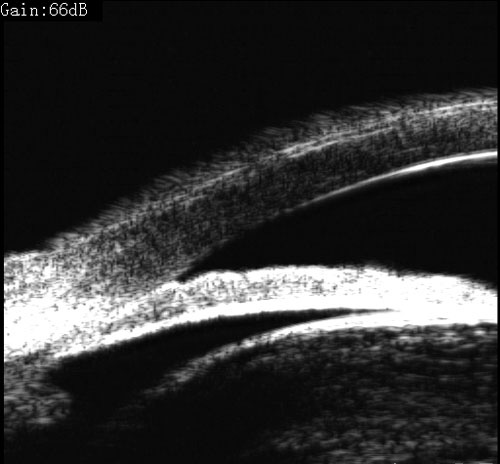

青光眼合并白内障